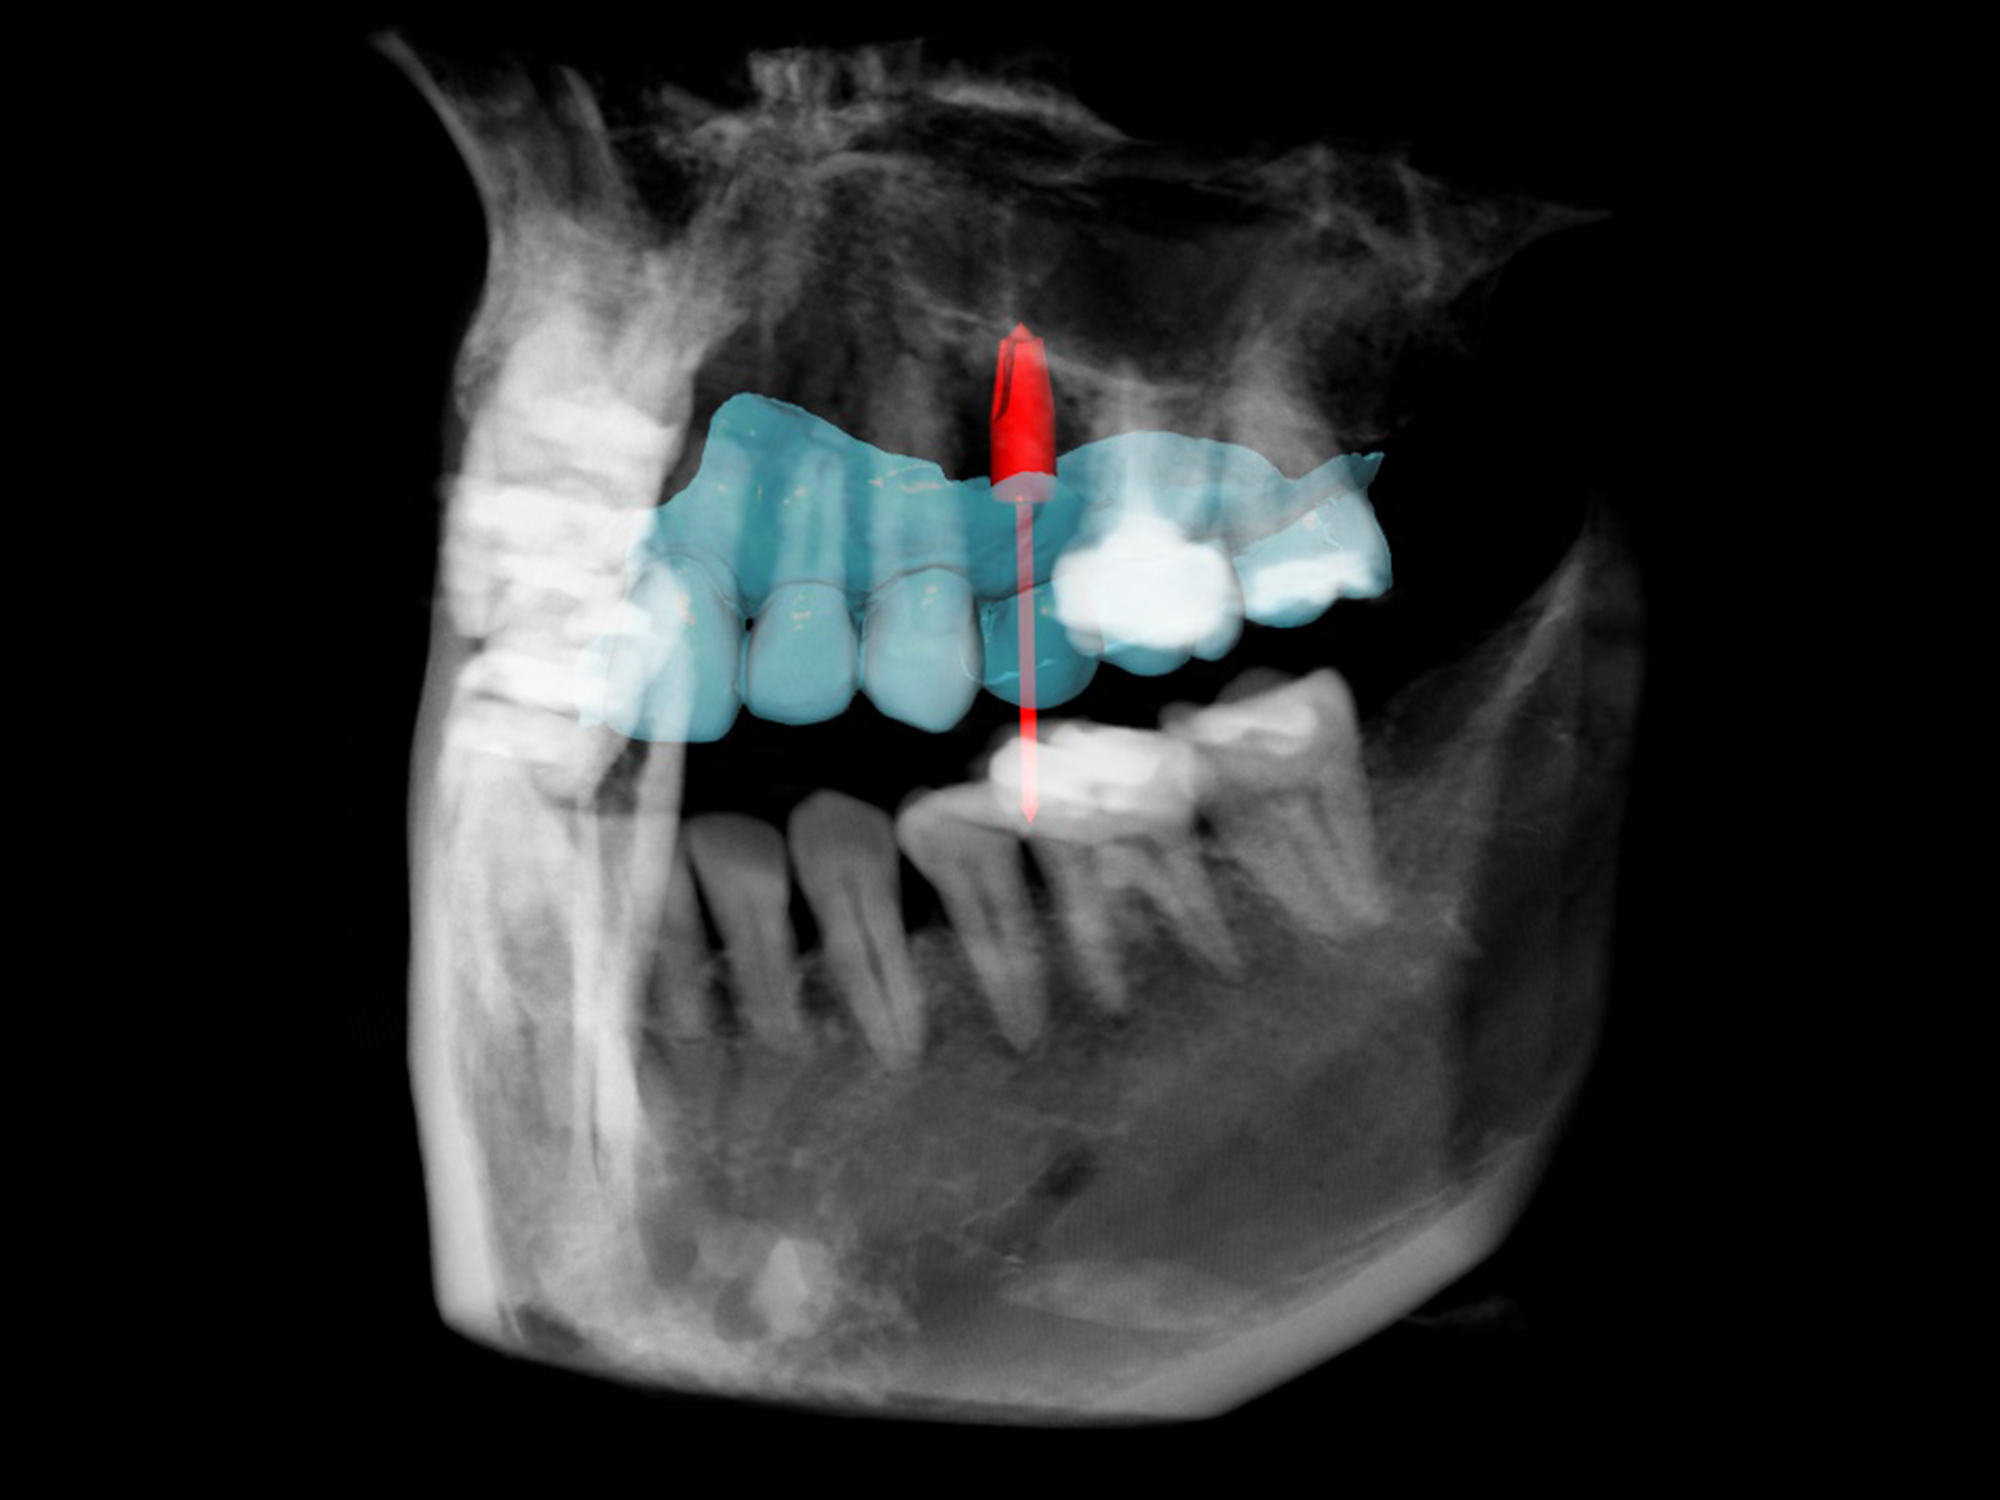

Advanced digital technology is used to scan, plan, and prepare a surgical guide for faster, minimally invasive, yet more precise implant placement with superior outcomes.

Intra-oral digital scanner and CBCT 3D imaging offer many advantages, including improved accuracy, efficiency, and patient experience.